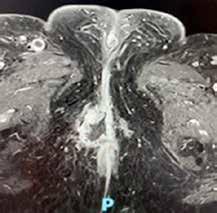

Figura 3.

Angiografía previa a la embolización con micropartículas. A través de la femoral, accedemos a la aorta (Ao). De la aorta accedemos a la arteria mesentérica superior (AMS), de donde sale en este caso la arteria hepática (AH). Se divide en arteria hepática derecha (AHD) y arteria hepática izquierda (AHI). Se emboliza la AHD y una rama distal de la AHI. Vemos cómo ambas ramas dan abundantes ramas que irrigan la lesión.